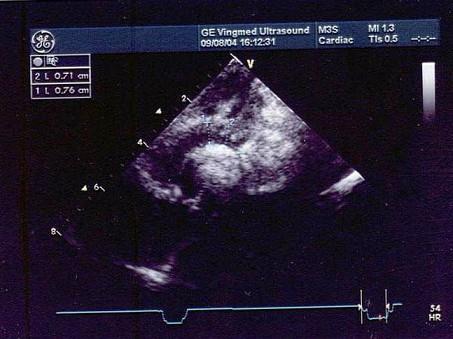

两个月患儿如图所示,该病例诊断最可能是?(?)A.主动脉弓扩张B.主动脉弓狭窄C.升主动脉扩张D.主动脉粥样斑块E.以上都不是

问题 两个月患儿如图所示,该病例诊断最可能是?(?)

选项 A.主动脉弓扩张 B.主动脉弓狭窄 C.升主动脉扩张 D.主动脉粥样斑块 E.以上都不是

答案 B